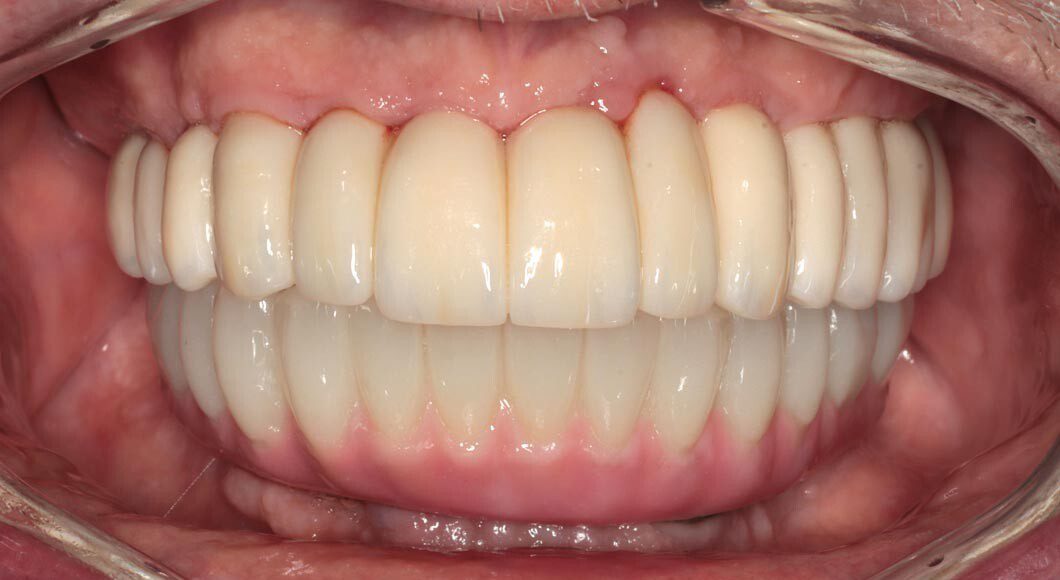

Prototype try-in, smile. The temporary bridges are removed and the prototypes placed. This is where the most scrutiny takes place as we want the patient and family to be thrilled with the appearance and bite. This is the last time changes can be made.